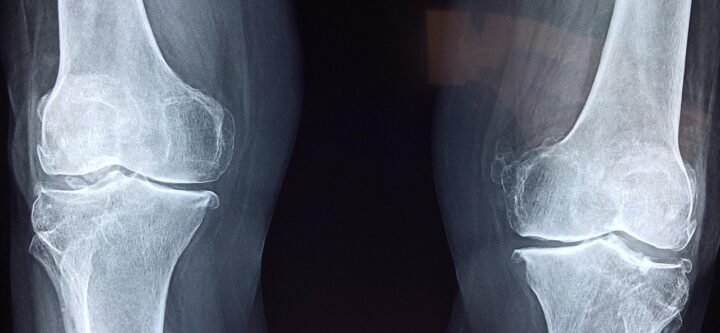

طب العظام في مركز سِتي كير الطبي، يقدم قسم طب العظام رعاية شاملة لحالات العظام والمفاصل والعضلات باستخدام أحدث التقنيات الطبية. نوفر علاجًا متخصصًا لجميع أنواع الكسور، سواء جراحيًا أو غير جراحي، بالإضافة إلى خطط رعاية شخصية للمرضى الذين يعانون من التهاب مفصل الركبة المزمن وألم المفاصل. يركز أطباؤنا أيضًا…